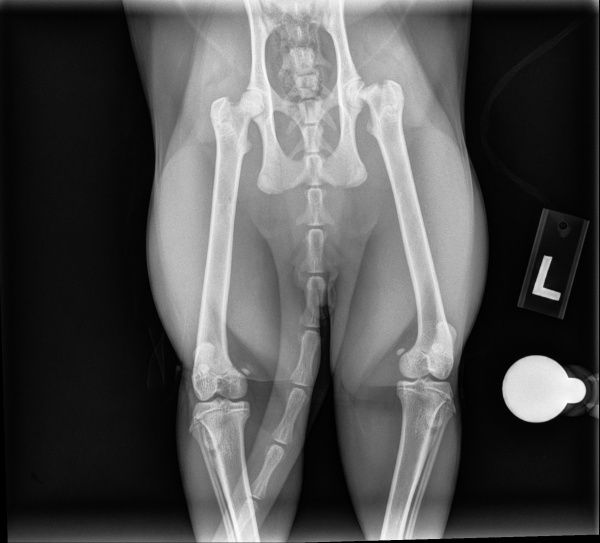

Radiographs of the pelvis and left femur were performed and reviewed by the IVS on staff veterinarian (Dr. Blong) and an IDEXX board-certified radiologist. Imaging revealed a complete, transverse Salter-Harris type I fracture of the left femoral head physis along with delayed physeal closure. This indicated that the fracture occurred at the growth plate and caused a slipped epiphysis.

Based on clinical findings and radiographic interpretation, Dorito was diagnosed with a left femoral head fracture.